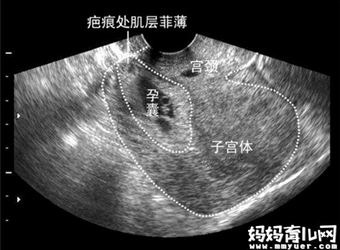

随着剖腹产率的上升,瘢痕妊娠的发病率也越多,但因为瘢痕妊娠除了个别孕妈会有腹痛、阴道少量出血外,早期和正常的妊娠没什么区别,所以很多孕妈即使是瘢痕妊…